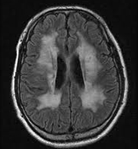

백질에는 광범위하게 탈수초(demyelination)가 일어납니다. 백질은 위축 상태이며, 말기에는 심하게 위축됩니다. 발병 연령과 효소 결핍의 종류에 따라 영아 후기형(late infantile), 연소형, 성인형 등으로 구분합니다.

이염성 백질이영양증은 혈청, 백혈구, 배양된 섬유아세포(fibroblast), 소변에서 아릴설파타아제 A(arylsulfatase A)가 감소, 소실되어 있으면 진단할 수 있습니다. 신속한 진단 방법으로는 요의 침전물에서 톨루이딘 블루(toluidine blue)로 metachromatic material을 증명하면 진단에 도움이 됩니다. 담낭에 술파타이드(sulfatide)가 축적되면 X-ray 검사로 나오지 않습니다. 말초신경의 전달 속도가 저하되며, 척수액의 단백이 증가합니다. 말초 신경 생검으로 이색 염색(metachromatic staining)을 확인할 수 있습니다. ARSA 유전자 검사로 유전적 진단을 할 수 있습니다. 양수 천자에 의하여 양수 세포를 배양하고, 아릴설파타아제 A(arylsulfatase A)를 측정하여 출생 전에 진단할 수 있습니다.